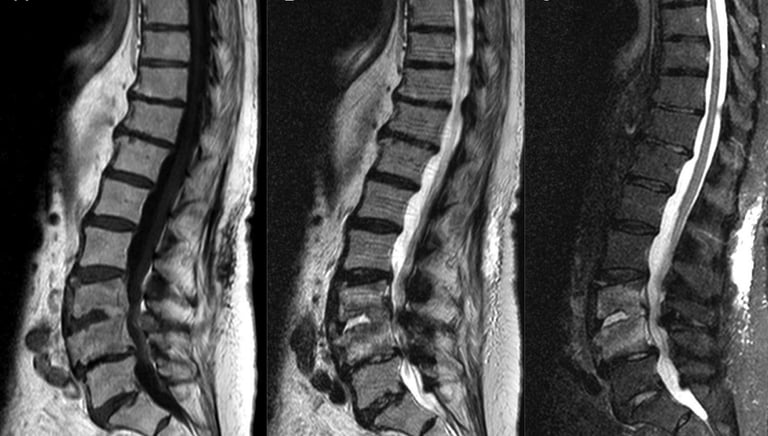

Initial assessment of bone damageMRI Scan

Best for identifying infection, nerve compression, and soft tissue involvementBiopsy